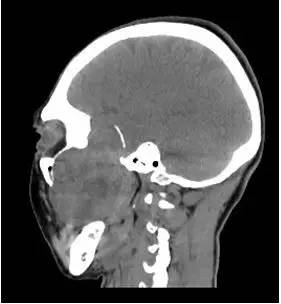

CT平扫矢状位重建

解析:本病例为中颅窝至颞下窝沟通性病变,对周围骨质主要呈膨胀压迫性改变,伴囊变、出血。

答案:C

病理:(中颅底内外沟通肿瘤) 神经鞘瘤,伴出血,局灶细胞较丰富。免疫组化结果显示:EMA(-), P53(-), S100(3 ), NF(-), PR(-), desmin(-), Ki-67( ,5-10%)

神经鞘瘤